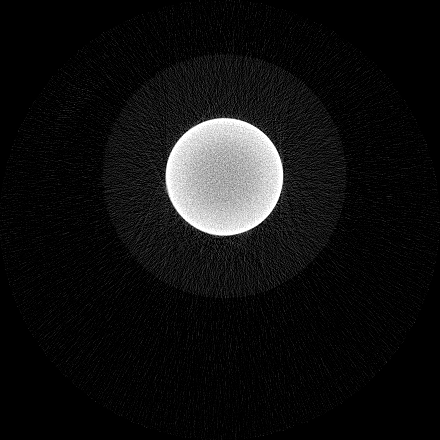

Beam hardening and metal artefacts pose challenges during CT imaging in the presence of metal hardware [17]. This paper presents data that demonstrates the use of spectral imaging in reducing beam hardening effects and metal artefacts. A high-Z sensor layer like CdTe is necessary to provide improved spectral resolution at higher x-ray energies needed for typical implant visualisation. Multi-energy acquisition of metal samples has the added advantage of capturing spectral information which exhibits reduced artefacts and reasonable non-metal (tissue) information. Further, the results were obtained without any hardware filters (except for the intrinsic filter-equivalent in the x-ray tube) and without any numerical corrections. A global reduction in noise due to charge sharing effects was seen due to the availability of CSM. 3D visualisation of the samples (figure 9) revealed finer spatial structures.